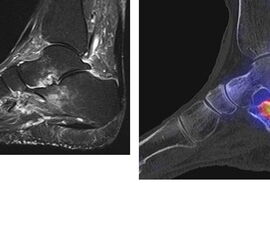

Abbildung 2.1.

Bildbeispiele symptomatische OCL

Zum Lesen der Bildbeschreibung und zur Vollansicht bitte das Bild anklicken. Bild: H. C. Rischke

Abbildung 2.2.

Bilder eines Patienten mit Z. n. mehrfachen Sprunggelenksdistorsionen in der Vergangenheit, besonders heftige Distorsion des linken Sprunggelenkes 5 Wochen vor der Untersuchung. Die SPECT/CT zeigt eine instabile osteochondrale Läsion mit deutlicher Aktivierung.

Abbildung 2.3.

Klärung bei Schmerzen im rechten OSG bei OCL an der medialen Talusschulter. Z. n. OSG-Distorsion vor 2 Jahren und Z. n. OSG-Fraktur / Syndesomosenruptur. Ausgedehnte OCL, hier jedoch kein erhöhter Knochenmetabolismus; lediglich Nachweis einer Stressreaktion im Bereich der Synchondrose eines Os trigonum als Schmerzursache.